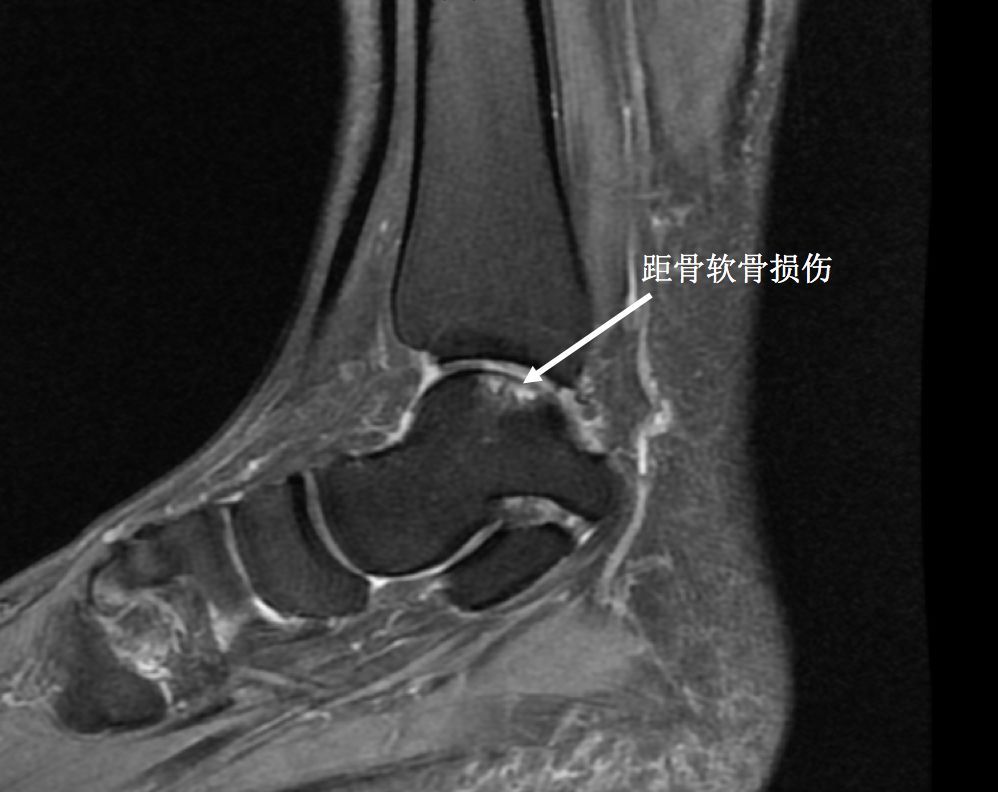

在日后生活中,由于踝关节反复多次扭伤,往往不可避免的会导致踝关节骨质增生导致踝关节出现撞击或者引起踝关节软骨损伤,而软骨损伤后很难自行恢复,行走时踝关节就会出现疼痛肿胀情况,到最后踝关节就会发生提前退变,导致踝关节性骨关节炎的提前到来。

(踝关节反复扭伤导致距骨软骨损伤)